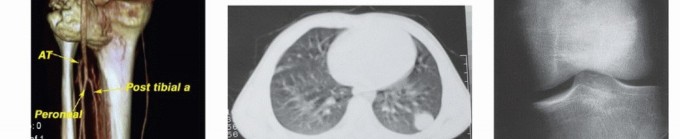

- Computed Tomography (CT): The modality of choice for assessing fine osseous detail, cortical integrity, and matrix mineralization. Thin-slice (≤1 mm) helical CT allows for precise 3D reconstructions. Intravenous contrast is essential to delineate the relationship of the soft tissue mass to major vascular bundles. Chest CT is mandatory for staging to rule out pulmonary metastases.

- Angiography and Venography: While largely supplanted by CT/MR Angiography, traditional angiography can map complex vascular displacements, identify feeding vessels for preoperative embolization (critical for hypervascular metastases like renal cell carcinoma), and assess the patency of collateral circulation prior to major vessel ligation. Venography can identify tumor thrombus or extrinsic venous compression.

Imaging Set 2: Advanced Diagnostic Modalities